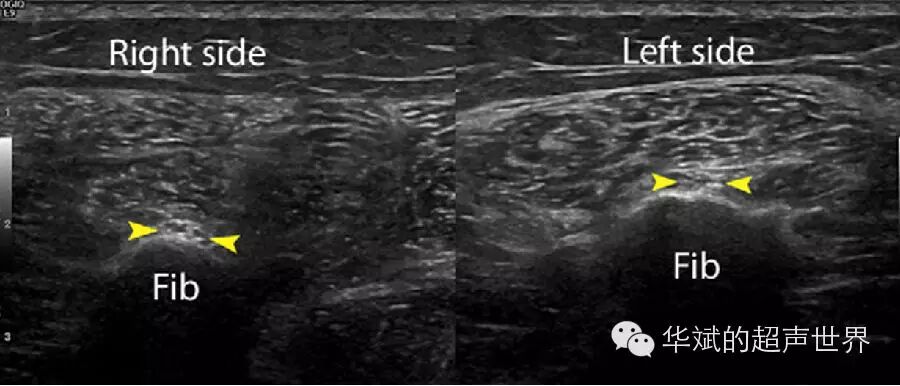

1. 以骨性结构作为标志(表三)。某些外周神经常常临近一些特定骨性解剖部位,超声检查时通过寻找这些骨性标志就可以定位具体的神经。例如:腓总神经在腘窝上缘自坐骨神经分出后向外绕过并紧贴腓骨颈向前向下再分出腓浅神经和腓深神经。因此,我们可以将腓骨颈作为定位腓总神经的重要标志(图7)。又如:肩胛上神经走形于冈上肌深方肩胛骨的肩胛上切迹内,超声检查时只要显示肩胛上切迹就可以定位肩胛上神经(图8)。

7 腓骨头处腓总神经。Fib腓骨颈部,三角箭头:腓总神经